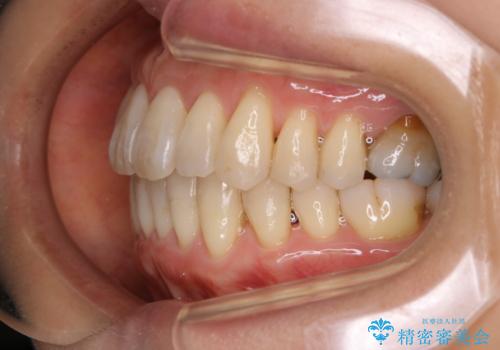

インビザラインによる非抜歯矯正を行いました。

IPRと呼ばれる、歯と歯の間を削る処置を行い、

がたつきを改善し歯を内側に入れることに成功しました。